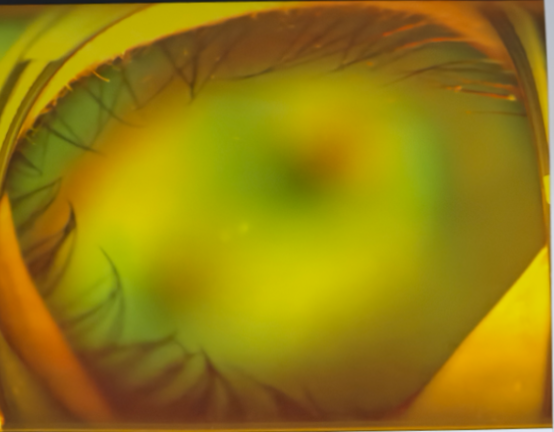

左眼術(shù)前△

視網(wǎng)膜脫離

左眼術(shù)后△